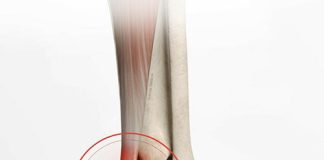

Aşil Tendon Rüptürü

Aşil tendonunun yırtılması, alt ekstremitede en sık görülen tendon yırtığıdır. Bu yaralanma genellikle üçüncü ile beşinci dekatlarındaki yetişkinlerde meydana gelir. Akut yırtılmalar, genellikle ani...